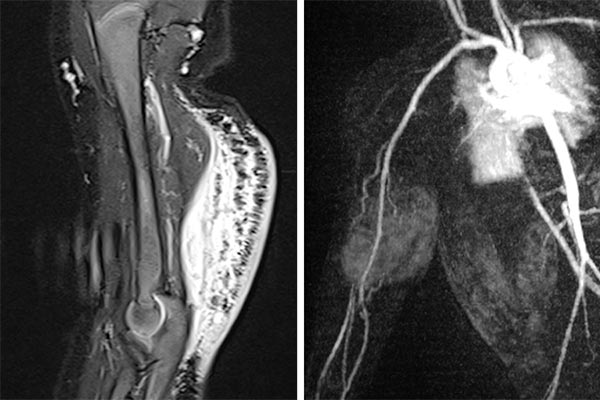

MRT Bildgebung (links – TIRM-Sequenz, rechts – dynamische MR-Angiographie). Nachweis unscharf begrenzter Signalanhebungen des dorsalen Oberarmes durch den Tumor mit senkrecht zur Haut verlaufenden hyperintensen Septen, entsprechend einem ausgedehnten lokalen Lymphödem. In der dynamischen MR-Angiographie Nachweis eines in der arteriellen Kontrastmittelphase hyperperfundierten Tumors mit klar erkennbaren arteriellen Feedergefäßen aus der A. brachialis.